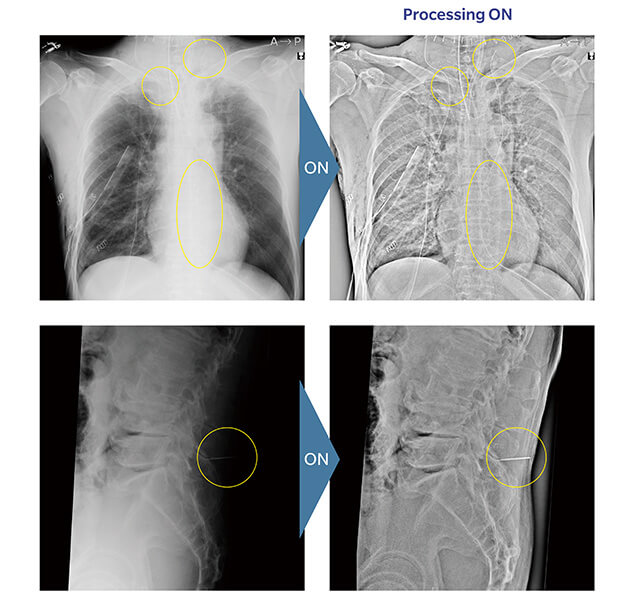

Tube and Gauze Image Enhancement

This image processing is specially designed to make it easier to check the remaining objects in surgical imaging and to confirm the position and route of the catheter tip.

Objects that are difficult to detect with normal image processing can be highlighted.